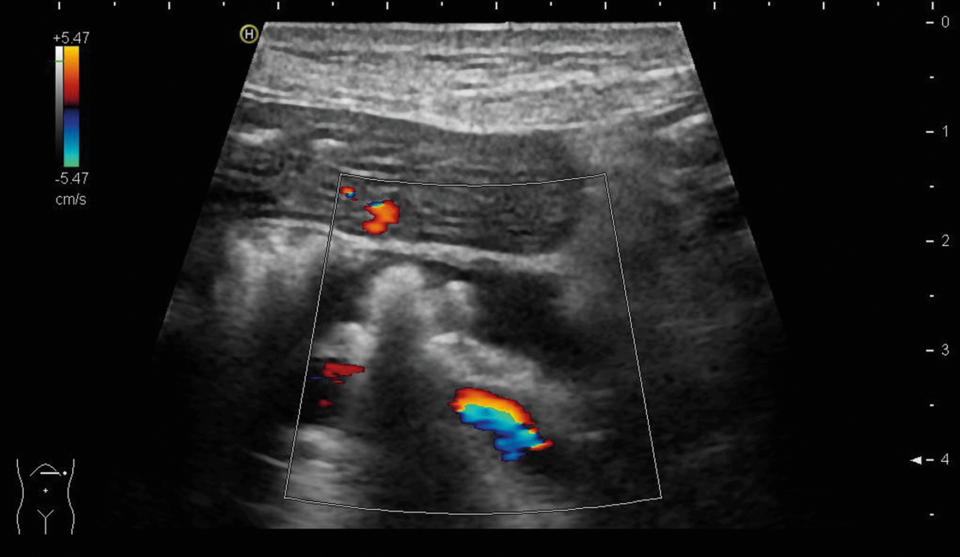

Pankreasgangsteine weisen auf eine chronische Pankreatitis hin. (Rechts: Dr. Peter Matheiowetz, Abteilung für Gastroenterologie und Hepatologie, St. Josefskrankenhaus Heidelberg) Pankreasgangsteine weisen auf eine chronische Pankreatitis hin. (Rechts: Dr. Peter Matheiowetz, Abteilung für Gastroenterologie und Hepatologie, St. Josefskrankenhaus Heidelberg) © Dr. P. Matheiowetz, St. Josefskrankenhaus Heidelberg; zVg

„Findet man bei der Ultraschalluntersuchung Pankreasgangsteine, kann die Diagnose einer chronischen Pankreatitis gestellt werden“, so Dr. Peter Matheiowetz vom St. Josefskrankenhaus Heidelberg. Bei der Patientin lag demnach ein Diabetes mellitus bei chronischer Pankreatitis vor, also ein so genannter pankreatogener bzw. Typ-3c-Diabetes.

Pankreasgangsteine weisen auf eine chronische Pankreatitis hin. Pankreasgangsteine weisen auf eine chronische Pankreatitis hin. © Dr. P. Matheiowetz, St. Josefskrankenhaus Heidelberg